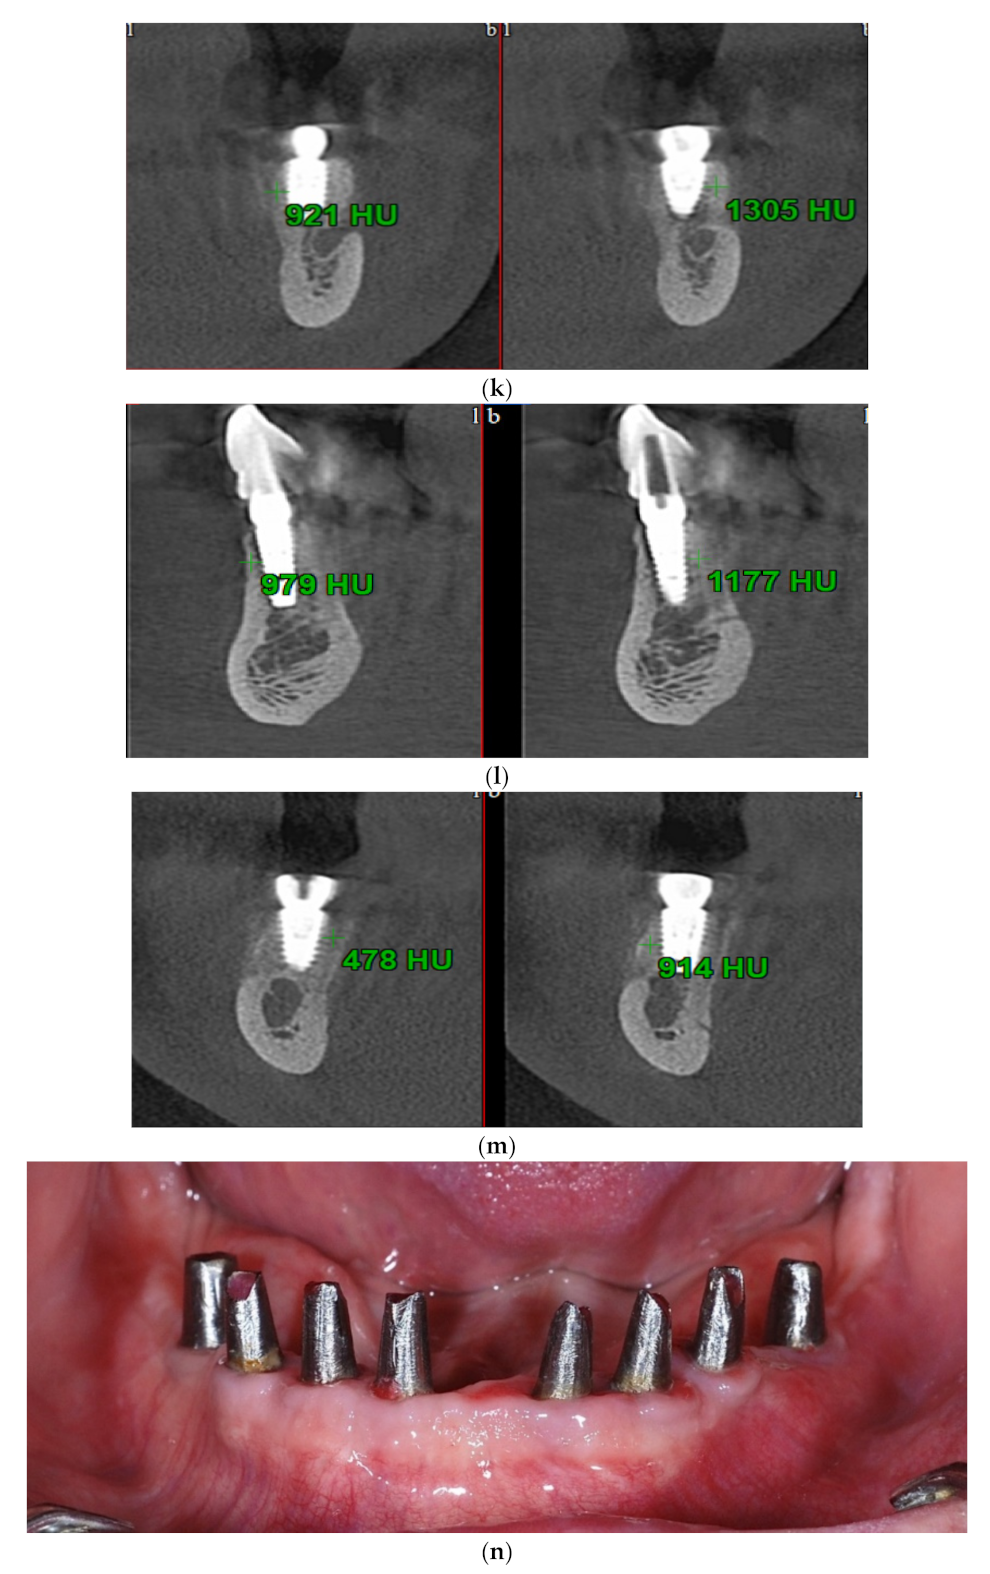

Intraoral view aspects and CBCT images of the implant sites, from a patient included in the test group, are presented in Figure 1a–o (reconstruction of the implant sites by S-GBR technique with porcine-derived xenograft material).

Figure 1.

(a) A.C., aged 65. Preoperatory intraoral view. (b) Preoperative CBCT images and alveolar bone parameters measured with Sidexis XG/ DVT (Densply/Sirona) software. (c) Intraoral view after the insertion of osteosynthesis screws and implants. (d) Intraoral view after the mandibular alveolar reconstruction with S-GBR technique and porcine xenograft. (e) Postoperative intraoral view after wound suture and temporary loading. (f) Alveolar bone width values measured at baseline (left) and at 6 months follow-up with Sidexis XG/ DVT software (Densply/Sirona). (g) Alveolar bone width values measured at baseline (left) and at 6 months follow-up with Sidexis XG/ DVT software (Densply/Sirona). (h) Alveolar bone width values measured at baseline (left) and at 6 months follow-up with Sidexis XG/ DVT software (Densply/Sirona). (i) Alveolar bone width values measured at baseline (left) and at 6 months follow-up with Sidexis XG/DVT software (Densply/Sirona). (j) Alveolar bone osteodensity values measured at baseline (left) and at 6 months follow-up (right) (implant site 4.1). (k) Alveolar bone osteodensity values measured at baseline (left) and at 6 months follow-up (right) (implant site 4.5). (l) Alveolar bone osteodensity values measured at baseline (left) and at 6 months follow-up (right) (implant site 3.2). (m) Alveolar bone osteodensity values measured at baseline (left) and at 6 months follow-up (right) (implant site 3.5). (n) Preloading intraoral view. (o) Postloading intraoral view.

Standardized measurements were taken for alveolar width preoperative and at 6 months postoperative. Implant sites width was measured before teeth extractions and 6 months after augmentation procedures. The osteodensity bone values were evaluated immediately after implant placement and at 6 months follow-up. Sidexis XG/ DVT (Densply/Sirona) software was used for the measurement of the width alveolar bone parameters at baseline and at 6 months follow-up. Width measurements were taken 3 mm, 5 mm, and 10 mm, respectively, from the crest at 3 intervals: the mesiodistal midpoint of the edentulous area and 3 mm mesial and distal to the midpoint. A mean value of width was calculated for each implant site preoperatively and at 6 months postoperatively. NNT Viewer/CT (NewTom) software was used to record the osteodensity values at baseline and at 6 months postoperative. The measurement of the preoperative osteodensity was performed immediately after implant placement and at 6 months follow-up. The bone density was measured in the areas adjacent to the implant, to the midpoint level.